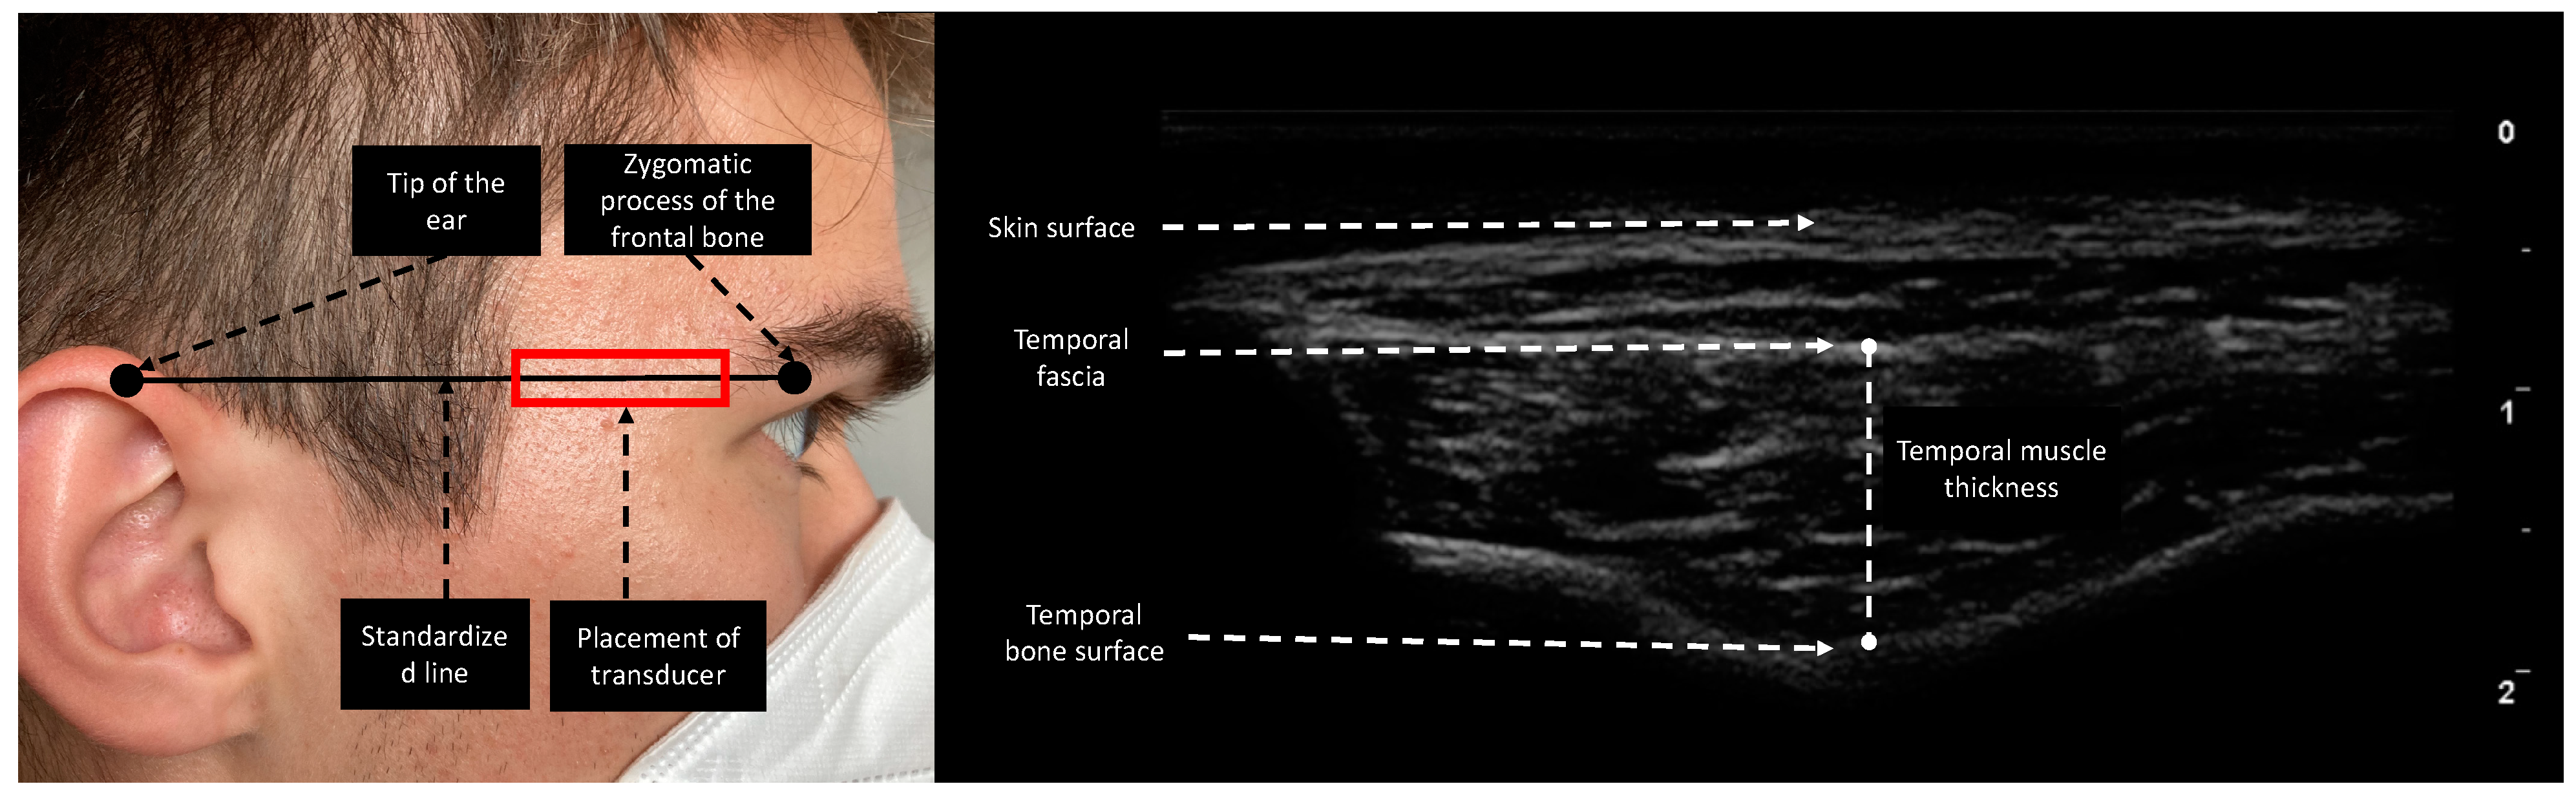

2. Materials and Methods